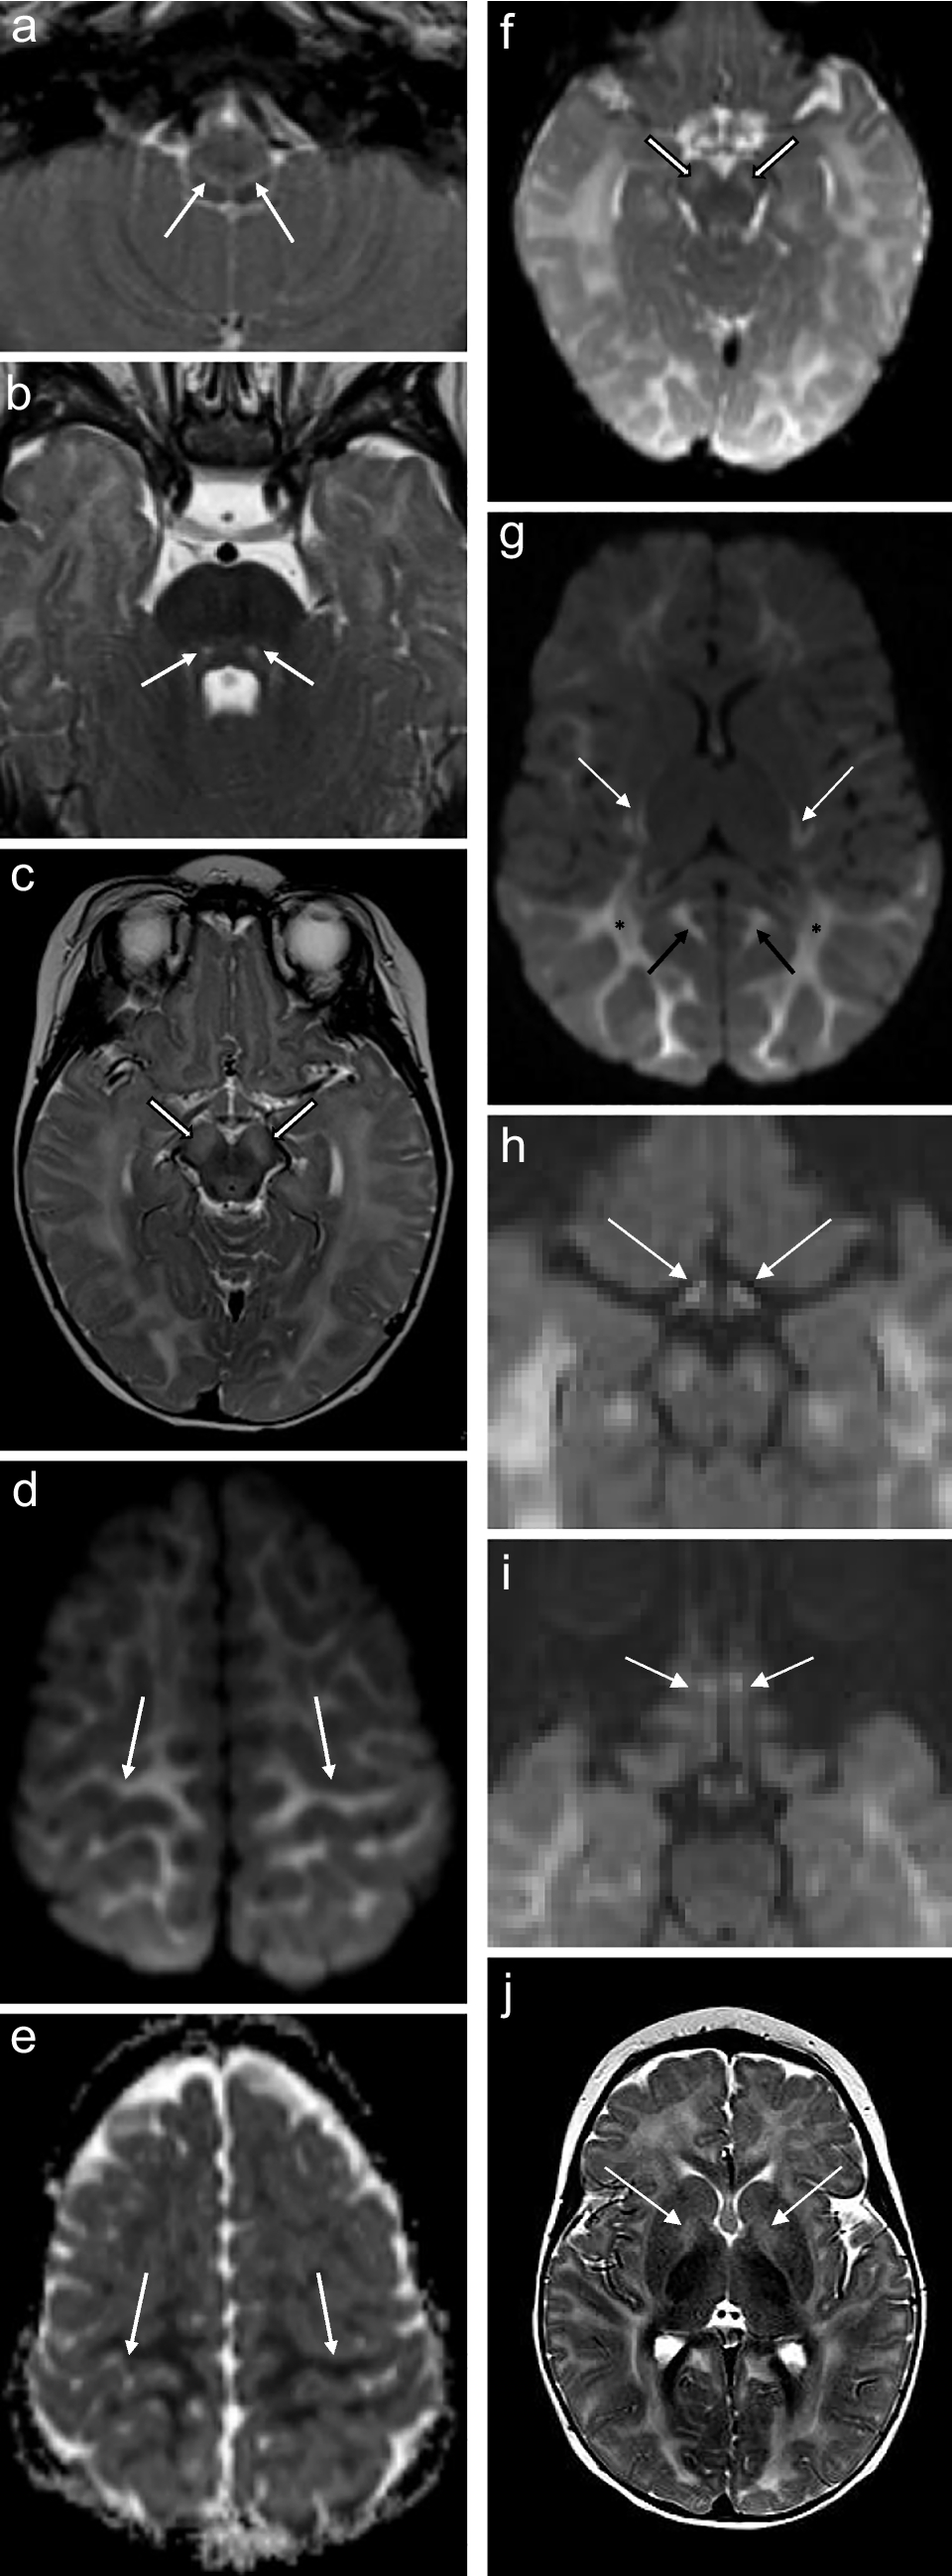

Fig. 2

A 2-week-old boy with genetically confirmed MPV17-related mitochondrial depletion syndrome. a Axial T2-weighted image shows hyperintense signal in the reticulospinal tracts of the proximal cervical cord (arrowheads). b Axial diffusion-weighted image and (c) apparent diffusion coefficient map demonstrate restricted diffusion in the cerebral peduncles (arrows). d Axial diffusion-weighted image and (e) apparent diffusion coefficient map demonstrate restricted diffusion in the globus pallidi (arrows). f Axial diffusion-weighted image and (g) apparent diffusion coefficient map demonstrate restricted diffusion in the subperirolandic white matter (arrows). h Axial diffusion-weighted image shows restricted diffusion in the medullary pyramidal tracts (arrows)

Brainstem

The brainstem was affected in four of eight (50%) patients and all signal changes were topographically localised to white matter tracts (Figs. 2 and 6). The 11-day-old had signal alteration conforming to the rubrospinal tracts in the midbrain. The 2-week-old had abnormal signal conforming to the corticospinal tracts traversing the cerebral peduncles of the midbrain and medullary pyramidal tracts of the ventral medulla. Both 8-month-old infants manifested T2 hyperintense signal in the cerebral peduncles as part of corticospinal tract involvement. Restricted diffusion accompanied white matter tract signal abnormality in all but one case.

Perirolandic cortex

Signal alterations in the sensorimotor cortex were identified in the two neonates (Figs. 1 and 2). This was differentiated from hypoxic ischaemic injury based on clinical histories which excluded perinatal asphyxia, the absence of characteristic changes in the basal ganglia-thalamus complex (posterolateral putamina and ventrolateral thalami), and the presence of restricted diffusion which would confine any potential hypoxic ischaemic injury to the acute phase. Perirolandic signal abnormality did not extend into the paracentral lobule [13].

Cranial nerves and nuclei

Half of the patients (50%) showed signal disturbances in these regions. One neonatal MRI revealed restricted diffusion in the midline tegmentum, near the oculomotor nuclei of the midbrain (Fig. 2). Three of the older infants’ (5 months to 8 months) MRI scans all demonstrated restricted diffusion in the optic chiasms and tracts, fornices, and olfactory nerves (Fig. 6).